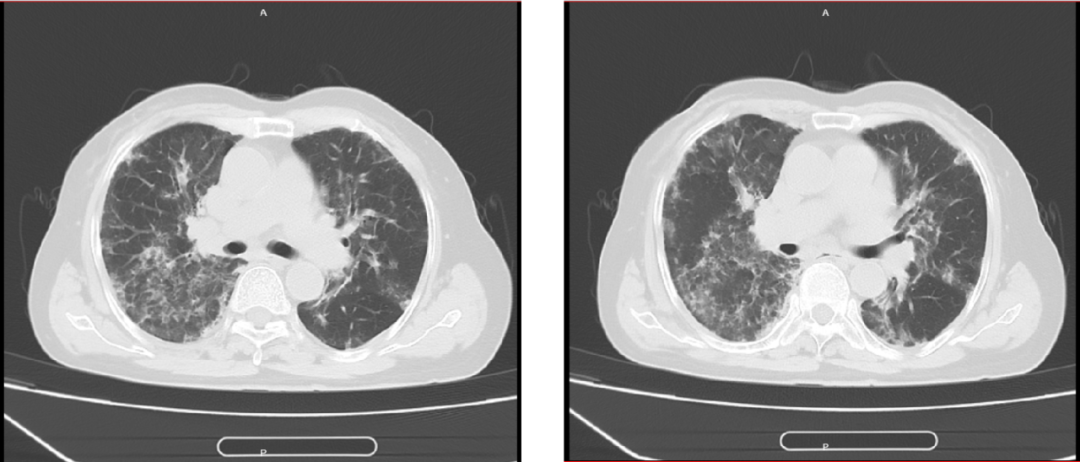

出院诊断:1.慢性嗜酸性粒细胞肺炎 2.支气管扩张

注意事项:口服醋酸泼尼松片2周后,复查CT。

糖皮质激素是治疗CEP的主要药物,多数患者激素治疗48小时内症状明显缓解,1周内影像学有吸收。起始口服泼尼松剂量0.5 mg/(kg•d),通常2~4周内减量,疗程以6~12个月为宜,低于6个月者容易复发。CEP的预后较好,单纯由CEP致死者罕见。